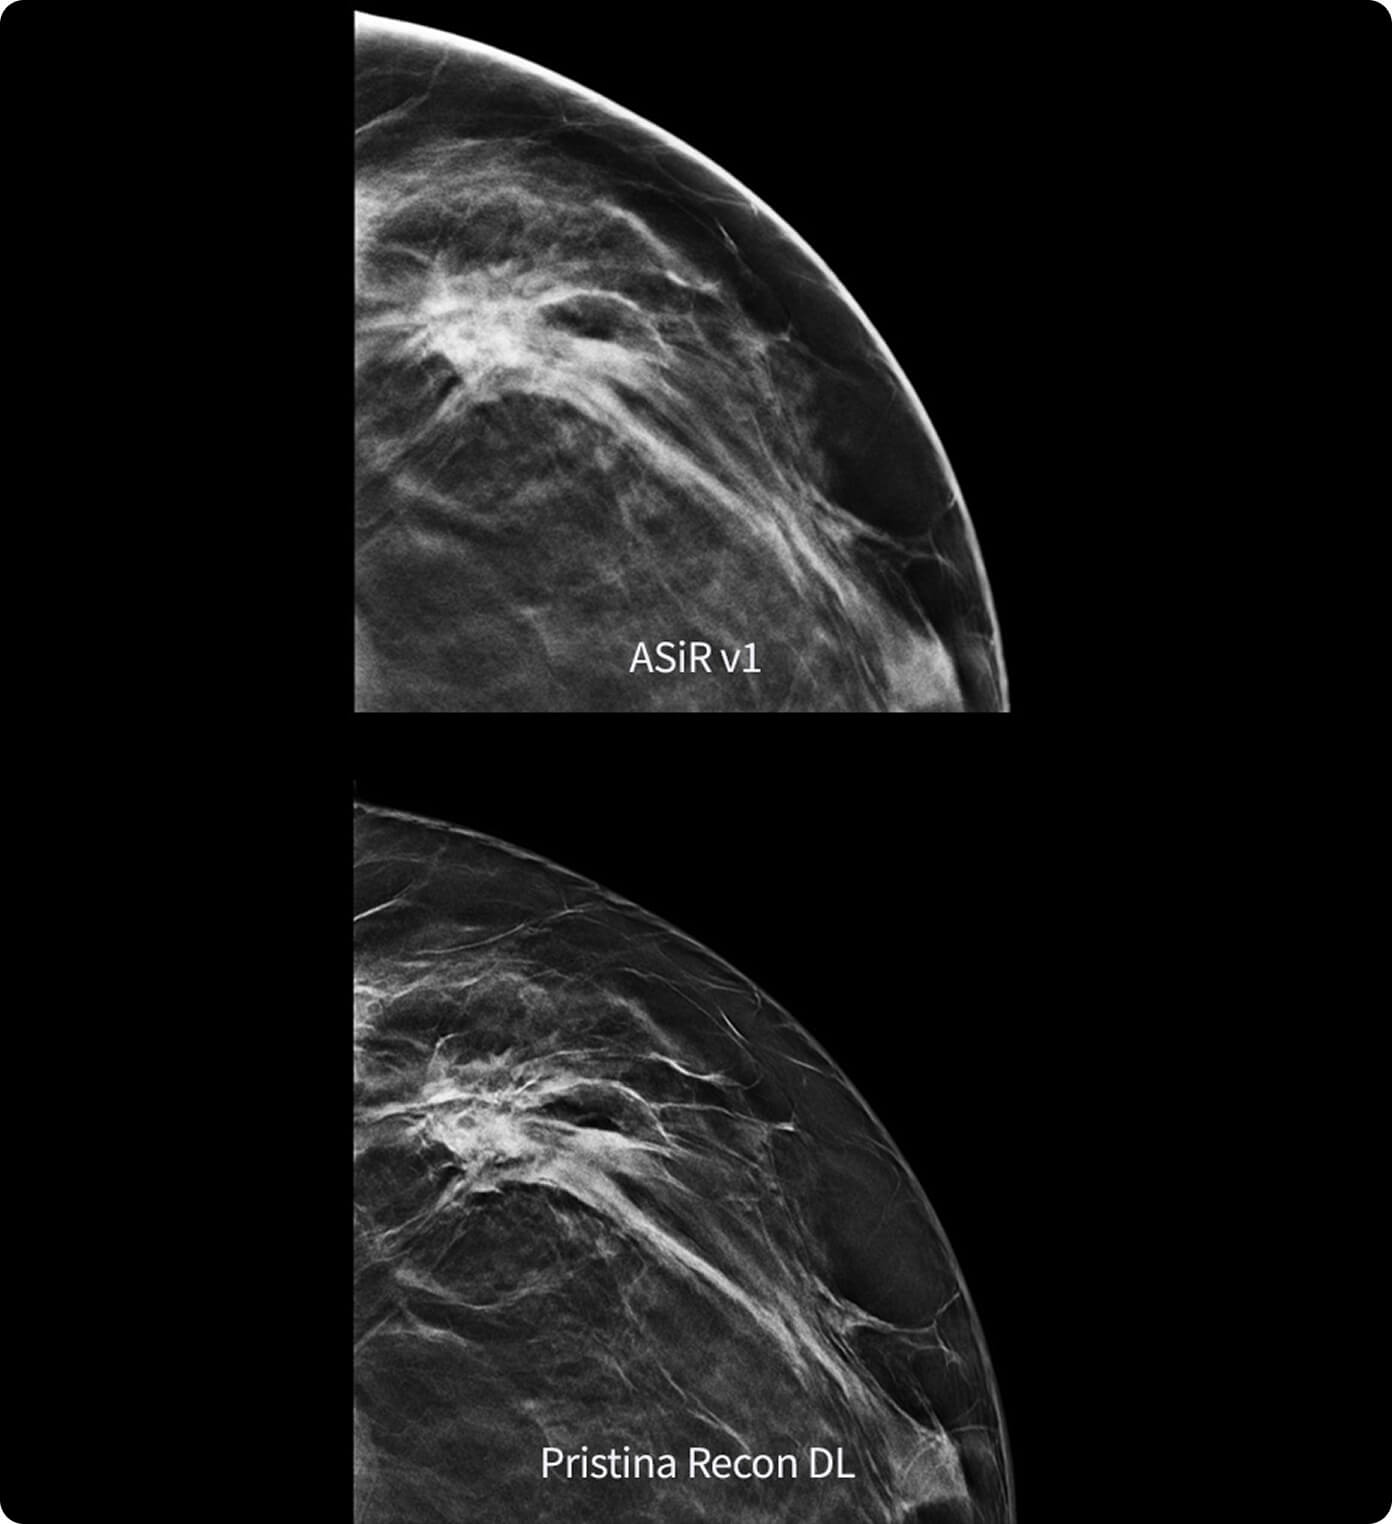

Alimentado por la tecnología SignalMax™, para que no tenga que comprometer la calidad de la imagen para la portabilidad